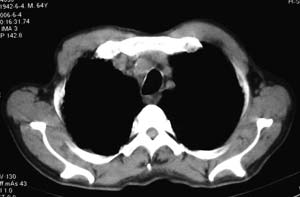

右侧胸廓略小于左侧,右肺上叶大片实变影,近肺门处密度较高,内见支气管气相,周围较淡,呈网格状,余肺野清晰,纵隔内见肿大淋巴结,右侧胸腔少量积液。临床 咳血,咳痰 发热 , 血象1.2万。

影像表现:肺窗示右肺上中叶均可见小片、条索状、小结状密度增高影,可见支气管充气相,小叶间隔增厚,支气管通畅,余肺未见明显异常。纵隔窗示4r可见小淋巴结融合,无明显肿大,右侧示少量胸腔积液。

右侧胸阔塌陷,纵隔右移。右上肺大片状高密度影,沿支气管血管束走行,内见点状钙化;支气管充气征阳性,支气管呈柱状扩张;胸膜下小叶间隔增厚;右侧后胸壁内侧见带状水样密度影;纵隔淋巴结增大。